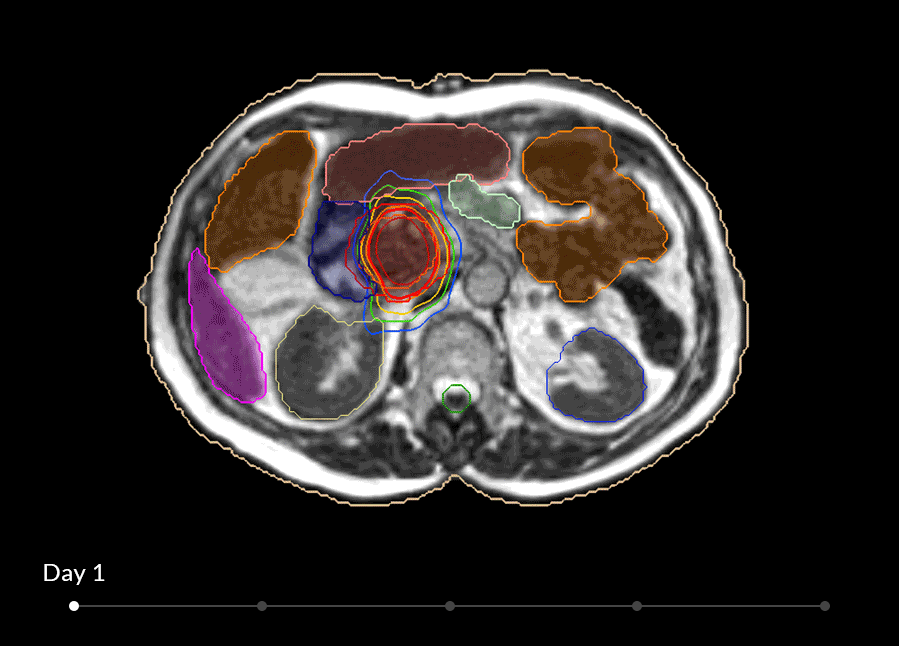

軟部組織の描出を得意とするMRIと放射線治療装置を組み合わせたMRリニアックシステム。放射線治療における次世代のソリューション。

MRIdianシステムを使用することによって、軟部組織を観察し、照射を視覚化して調整し、治療をコントロールすることが可能です。